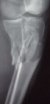

Enes Kanlic 18 Декабрь 2003, 10:08

1

2

3

4

5

6

I agree with Dr. Wilson,

In general:

1. Nailing proximal tibias: Starting point has to be high (still not to

penetrate knee capsule) and a little bit lateral from midpoint. Blocking

screws are very helpful and sometimes necessary, see attached Slides 1 and

2).

2. Plate could be used, just needs to be done right (minimally invasive,

preservation of soft tissues, slides 4 and 5)

3. If it is impossible to get reduction trying to pass the nail distally,

plate could be added (as on slides 5 and 6).

In this particular patient, if soft tissues are good, I would:

A) Exchange (closed method) the nail (shorter one, starting point a little

bit more lateral) and blocking screws probably would be needed, and if that

does not work

B) I would open the fracture, would help my reduction with forceps or plate

and still nail it.

If somebody is not comfortable with this techniques, probably the safest way

(not and most comfortable and convenient for the patient) is to go for ring

external fixator (Ilizarov type).